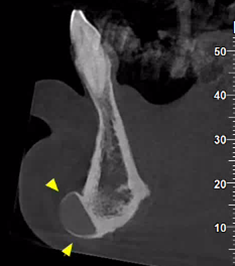

Εκτός από τις παραπάνω ελάχιστα επεμβατικές τεχνικές, στις απεικονίσεις της τραχηλοπροσωπικής χώρας μπορεί να συναντήσουμε και τα αποτελέσματα πιο επεμβατικών τεχνικών, όπως διάφορες μορφές πλαστικής χειρουργικής με χρήση ενθεμάτων σιλικόνης.

Ένα παράδειγμα είναι η γενειοπλαστική, όπως φαίνεται στην παρακάτω περίπτωση.